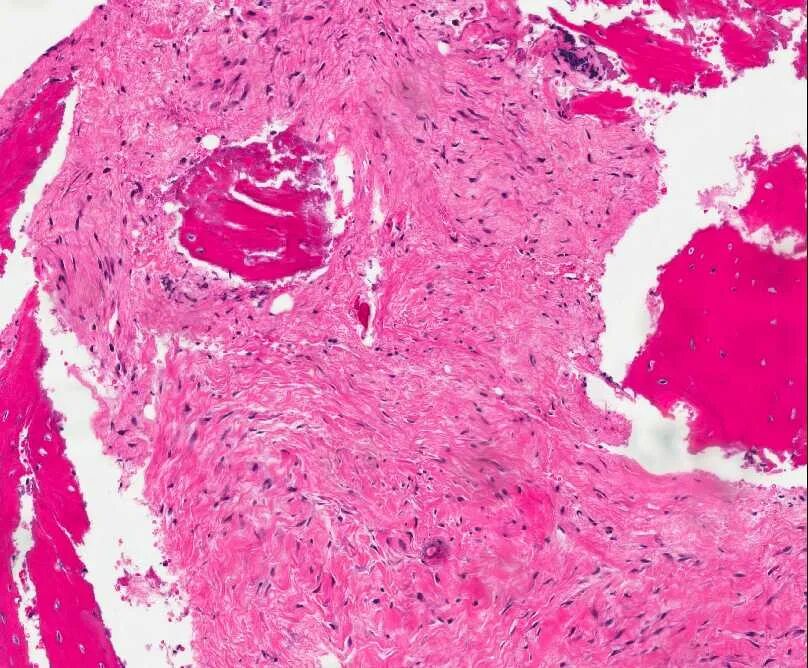

Гистология фото